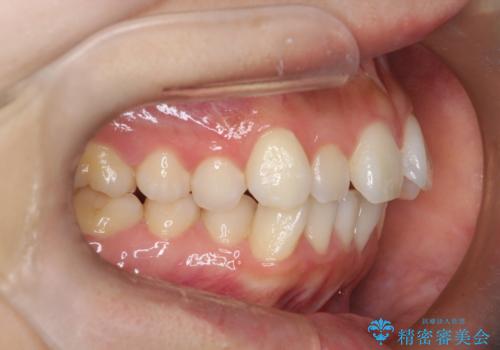

- 前歯の凸凹と口元の突出感を主訴に来院されました。

臼歯関係が上顎前突傾向のため、上の小臼歯を抜歯してワイヤー矯正を行なっております。

下顎の叢生はIPRを行なって配列しています。